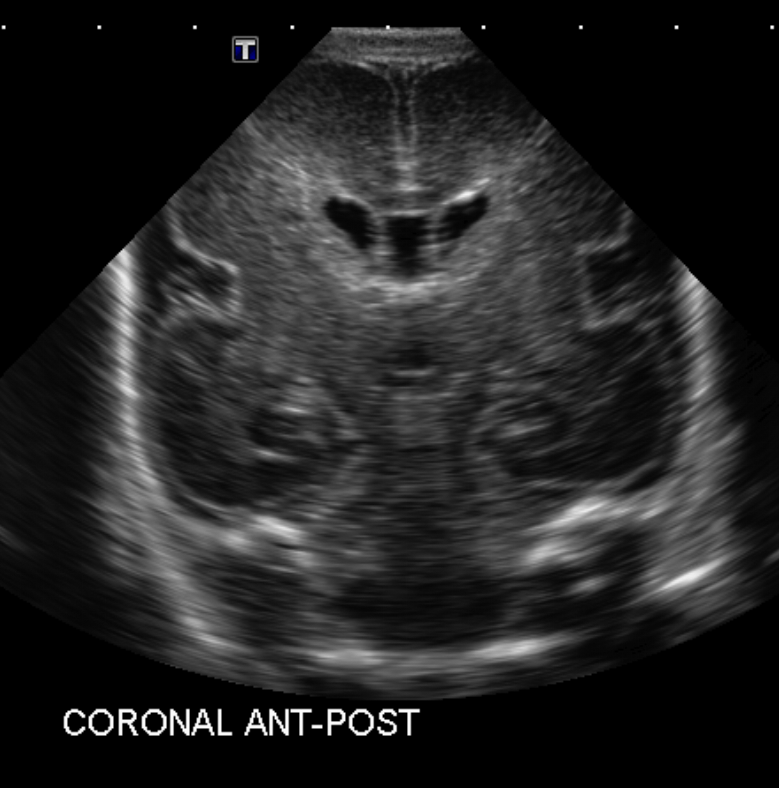

Section 1 Submit Findings Case151 Findings Brain The brain is immature. Yes No There is under-sulcation and open sylvian fissures. Yes No There is/are multiple hypoechoic areas in the periventricular white matter. Yes No There is/are multiple hyperechoic areas in the periventricular white matter. Yes No There is diffuse cerebral edema with diffusely increased echogenicity of the brain parenchyma and loss of grey white matter differentiation. Yes No The thalami/basal ganglia are hypoechoic. Yes No There is periventricular calcification. Yes No There is intra-parenchymal calcification. Yes No CSF spaces/ventricular system There is a prominence of the extra axial fluid spaces. Yes No There are debris/septations in the extra axial fluid spaces. Yes No There are debris/septations in the ventricles. Yes No There is a subdural collection on the right/left side. Yes No There is prominence of the ventricular system. Yes No There is an asymmetry of the ventricular system. Yes No There is a cavum septum pellucidum. Yes No There is a midline shift towards right/left. Yes No The choroid plexus is bulky/lobulated. Yes No There is a choroid plexus cyst measuring… Yes No There are debris/clots in the occipital horn. Yes No There is a posterior fossa cyst measuring… Yes No The tentorium is elevated/depressed. Yes No The lateral ventricle/s are dilated. Yes No The third ventricle is dilated. Yes No The 4th ventricle is dilated. Yes No There are pseudo cysts. Yes No Germinal matrix hemorrhage (Only in the premature infants): Please do not answer if the patient is a full term. There is a germinal matrix hemorrhage, consistent with a grade I hemorrhage. Yes No There is an intraventricular extension consistent with a grade II hemorrhage. Yes No There is an intraventricular extension with the dilatation of ventricles, consistent with a grade III hemorrhage. Yes No There is an intra-parenchymal extension, consistent with grade IV hemorrhage. Yes No On color Doppler examination, the Resistive index in the anterior cerebral artery is… There is a loss of the diastolic flow on the Doppler exam. Yes No There is altered vascularity on Doppler imaging. Yes No There is an AVM in the region of… Yes No